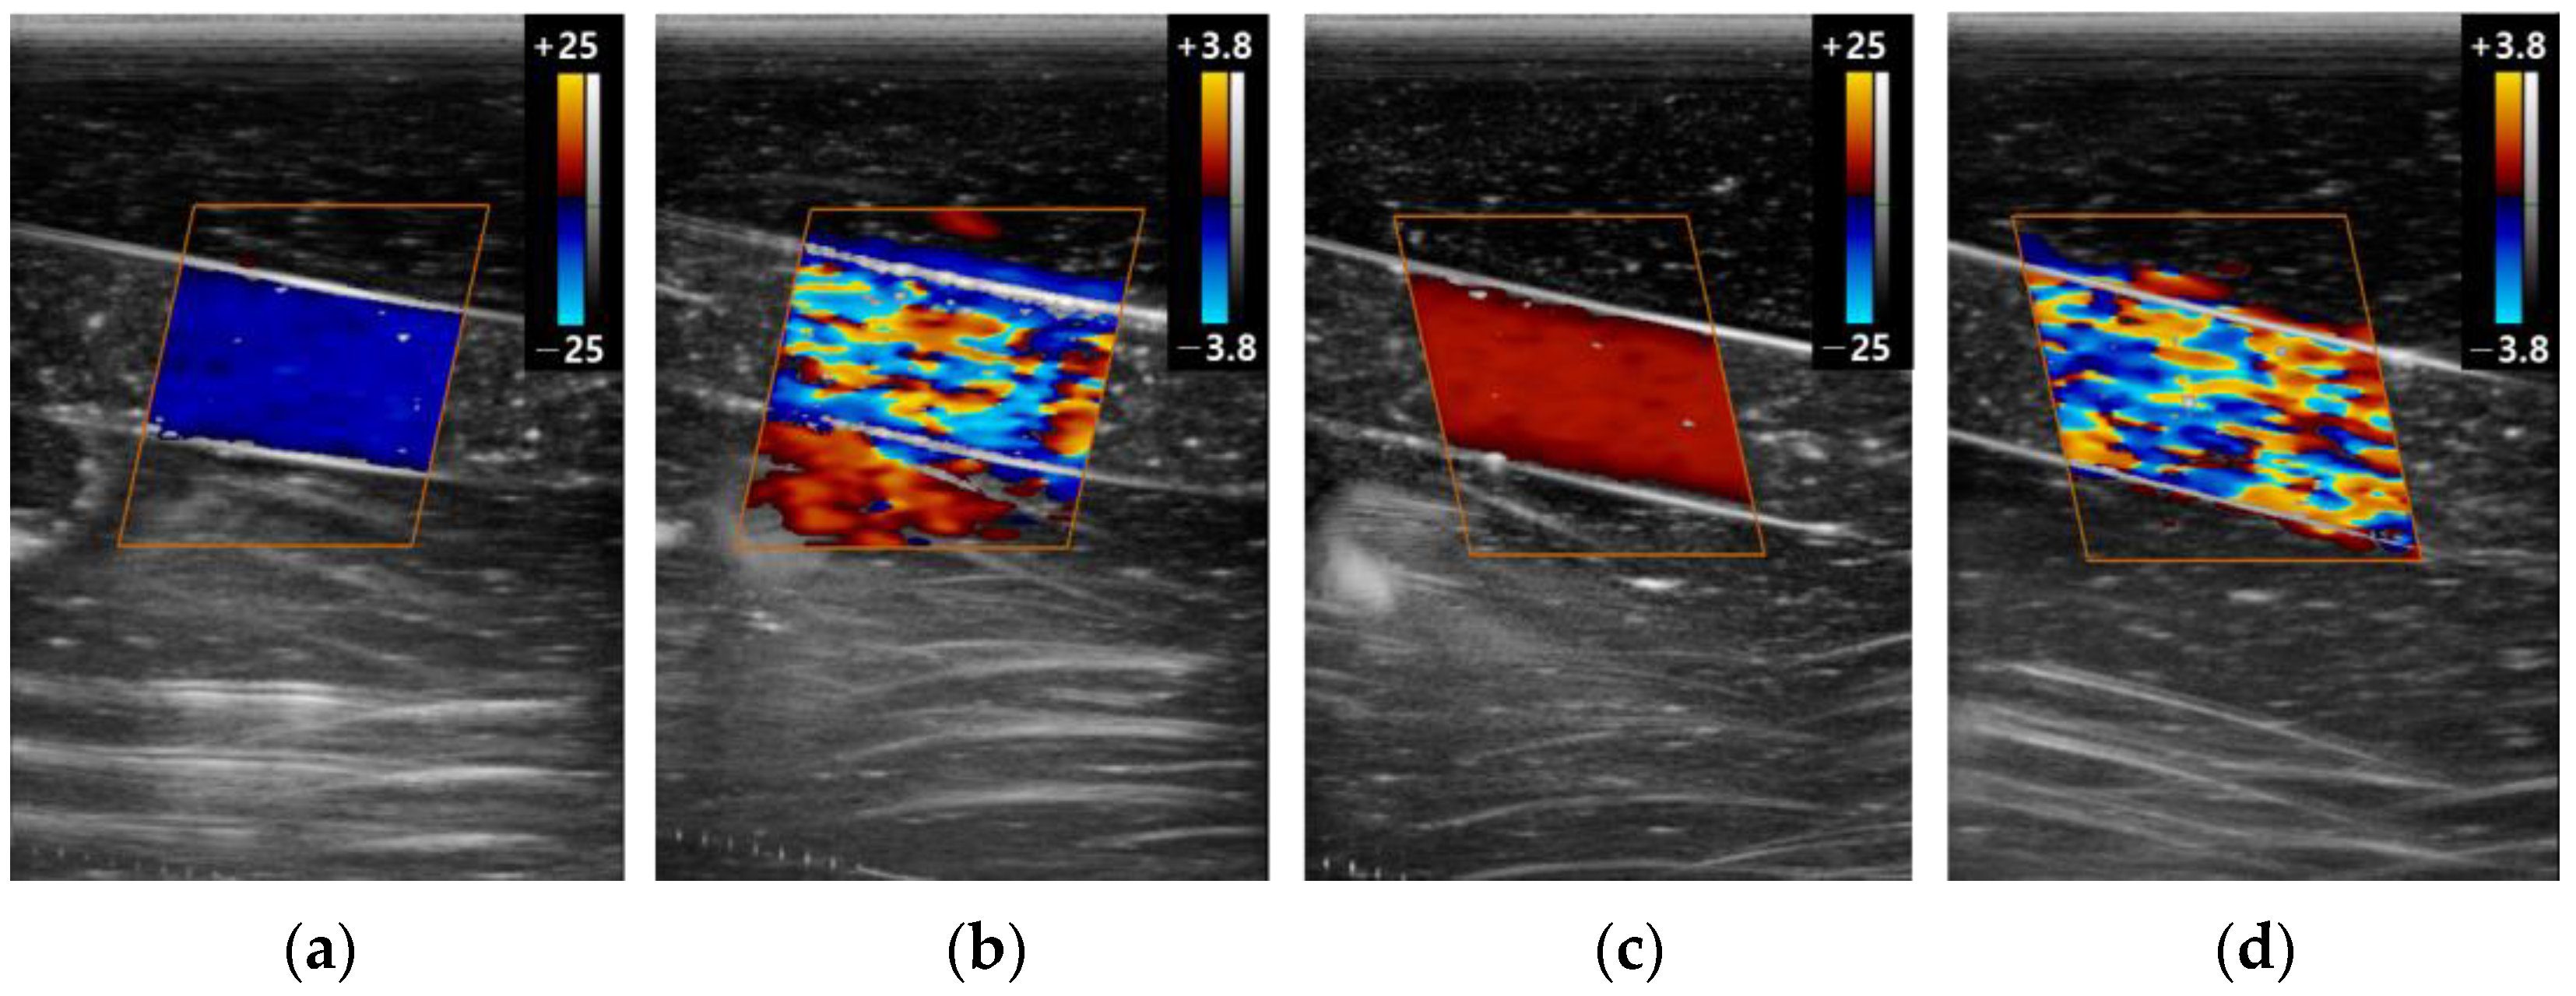

3.2. The Color Doppler Results

3.2.2. Scale